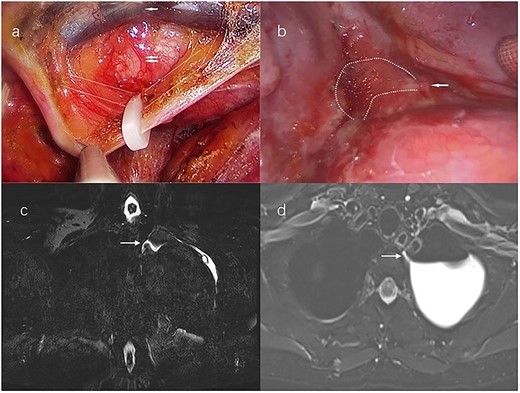

A 54-year-old woman without a history of smoking visited our hospital. The chest computed tomography (CT) revealed a 3.5 × 2.4 cm irregular soft tissue mass in the apicoposterior segment of the left upper lobe. All other examinations were within normal limits. For diagnosis and radical therapy, we performed left upper lobe wedge resection by uniport video-assisted thoracic surgery (VATS). Its histological finding was tuberculoma. Then we did not dissect the mediastinal lymph node. Upon beginning a regular diet postoperative day 1 (POD 1), the patient did not have any special discomfort and pleural fluid drainage was normal. But on POD 2, milky fluid was drained (700 ml/24 h) and the triglyceride level in the pleural fluid was 378 mg/dl. The patient was diagnosed with chylothorax. First, the patient received in total a series of conservative treatment measures, including total parenteral nutrition and drug therapy (somatostatin), but it had no great effect on the pleural fluid drainage volume. Until POD 7, the volume was still >500 ml/day. Therefore, she underwent conventional right supradiaphragmatic thoracic duct ligation by uniport VATS (Fig. 1a) But the condition was no improvement, and even developed high-volume, milky pleural fluid drainage >1200 ml/24 h on POD 8. Then, the patient underwent a magnetic resonance–thoracic discography (MRTD). The MRTD revealed that the thoracic duct fistula was located at the left posterior part of the esophagus at the T2–T3 level of the left chest. From the coronal view (Fig. 1c) and axial view (Fig. 1d), the relationship between the chylothorax and the thoracic duct fistula was clearly shown. Then she underwent the third operation, ligating the thoracic duct fistula by uniport VATS on POD 19 (Fig. 1b). Immediately after surgery, the fluid drainage dropped to <150 ml/day and no chyle leakage occurred. The patient gave informed consent to this study.

(a) Uniport video-assisted thoracic surgery (VATS) right supradiaphragmatic thoracic duct ligation; white broken lines mark the course of the thoracic duct; the single white arrow marks the aorta, the double white arrows mark the azygos vein. (b) Left lateral uniport VATS reveals that the thoracic duct fistula locates at the T2-T3 level; chylous pleural effusion flows from the fistula; the single white arrow marks the thoracic duct fistula; the white broken lines mark the chylous pleural effusion. (c) Magnetic resonance–thoracic discography reveals that the thoracic duct fistula is located at the left posterior part of the esophagus at the T2-T3 level; the single white arrow marks the thoracic duct fistula in the coronal view. (d) The thoracic duct fistula is connected to the pleural effusion in the Axial view; the single white arrow marks the thoracic duct fistula.